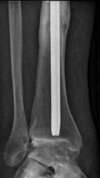

arthrose de cheville post traumatique

arthrodèse de cheville par vissage en croix avec greffe fibulaire vissée